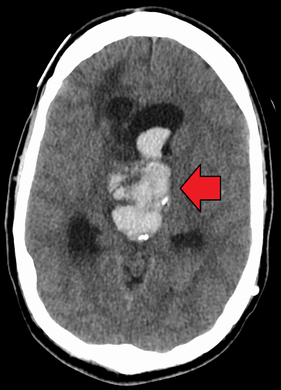

Axial CT scan of a spontaneous intracranial hemorrhage

Intracranial hemorrhage (ICH), also known as intracranial bleed, is bleeding within the skull.[1] Subtypes are intracerebral bleeds (intraventricular bleeds and intraparenchymal bleeds), subarachnoid bleeds, epidural bleeds, and subdural bleeds.[2] More often than not it ends in a lethal outcome.